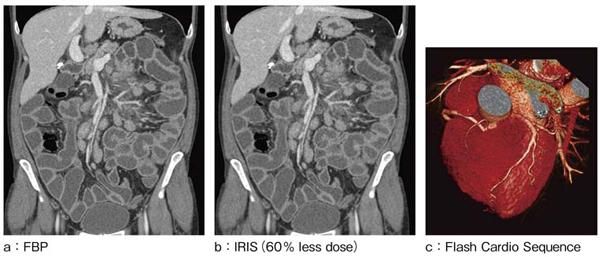

画質や細部の描出を損なわずにノイズが抑えられ,日常的な臨床使用を実現し,結果として,最大60%の被ばく低減が可能となった(図3 a,b)。また,これまでになし得た被ばく低減技術との併用により,例えば,心臓CT検査を0.36mSvという超低線量で行うことも可能である(図3 c)。

a:通常線量のスキャンデータにフィルタ補正逆投影(FBP)法による画像再構成を行った画像

b:aより60%低い線量でのスキャンデータにIRISを用いて画像再構成を行った画像。IRISを用いて画像再構成を行った画像は,大幅に低い線量でスキャンしたにもかかわらず同等のノイズレベルを実現。

c:Flash Cardio Sequenceモードで撮影。75msの時間分解能とECG-dose modulationの併用により,超低線量撮影(0.36mSv)を実現。